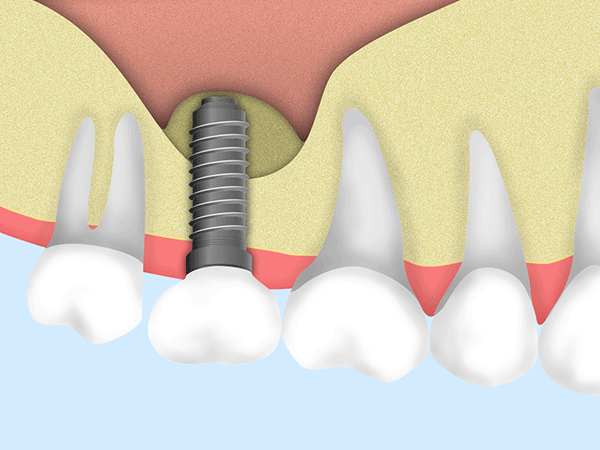

インプラント治療は、顎の骨にインプラント(人工歯根)を埋め込み、その上にセラミック製の人工歯や特殊な入れ歯を装着して歯の機能を補う治療法です。

顎の骨としっかり結合するため、自分の歯で噛んでいるのに近い自然な噛み心地が得られます。見た目も自然で、見た目と機能の両方を回復できる治療です。